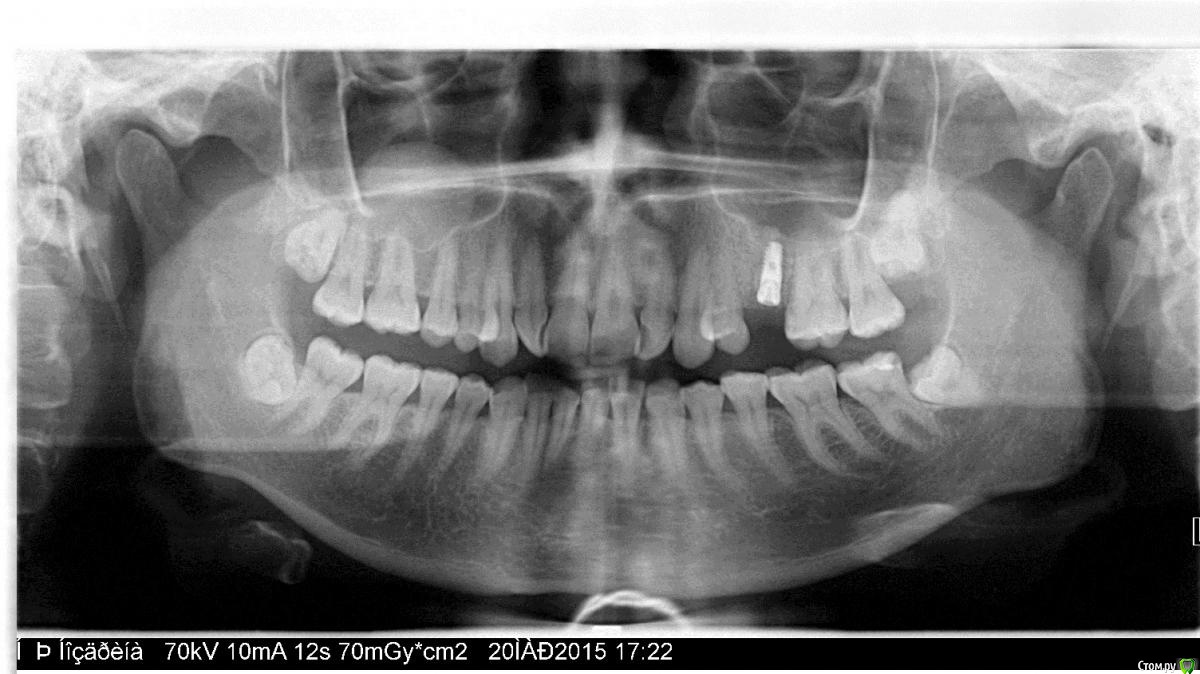

Большой Зеленый Опубликовано 29 сентября, 2015 Поделиться Опубликовано 29 сентября, 2015 В гайморовой пазухе справа киста. Обратите внимание. Консультация ЛОРа не повредит. Ссылка на комментарий

Natalia_ Опубликовано 29 сентября, 2015 Автор Поделиться Опубликовано 29 сентября, 2015 В гайморовой пазухе справа киста. Обратите внимание. Консультация ЛОРа не повредит.Cпасибо, я знаю, она давно уже,.. сказали, пока можно с ней еще походить. Ссылка на комментарий